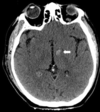

Describe

traumatic subdural hematoma